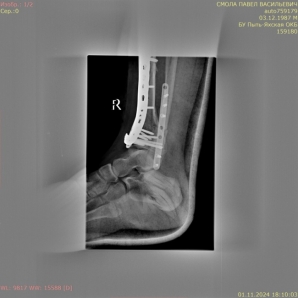

1) Мужчина, 35 лет. ДТП, водитель. Поступил в экстренном порядке. Диагноз — закрытый оскольчатый перелом дистального метаэпифиза правой большеберцовой кости, перелом наружной лодыжки правой голени со смещением отломков (рис. 1).

Рис. 1.